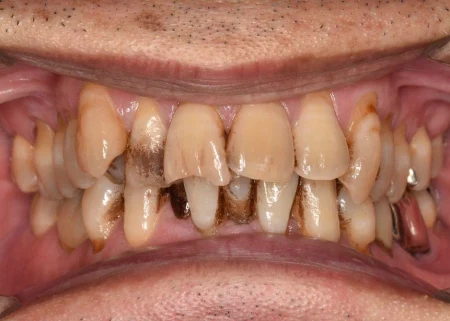

治療後

| 術後の経過・現在の様子 | 着色がきれいに取れて歯本来の自然な白さになり、歯肉も引き締まって歯周病が改善されました。 患者様も「歯がきれいになってうれしい。舌触りも変わった」と喜ばれていました。 現在は、最初にご相談いただいた詰め物のやり直しを進め、より美しく健康な状態となってきています。 |